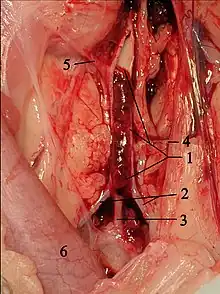

.jpg)

A diagnosis of hypertrophic cardiomyopathy is based upon several features of the disease process. While there is use of echocardiography, cardiac catheterization, or cardiac MRI in the diagnosis of the disease, other important considerations include ECG, genetic testing (although not primarily used for diagnosis),[35] and any family history of HCM or unexplained sudden death in otherwise healthy individuals. In about 60 to 70% of the cases, cardiac MRI shows thickening of more than 15 mm of the lower part of the ventricular septum. T1-weighted imaging may identify scarring of cardiac tissues while T2-weighted imaging may identify edema and inflammation of cardiac tissue which is associated with acute clinical signs of chest pain and fainting episodes.[36]